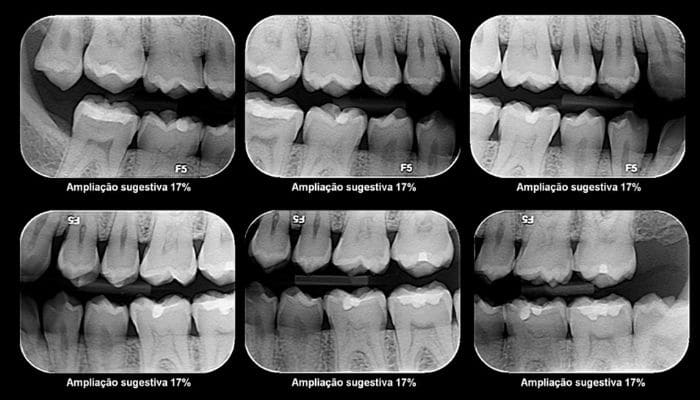

Apicectomia

1 – Tratamento de Canal – permite salvar o dente comprometido e aliviar a dor do paciente.

2 – Cirurgia – remoção da ponta da raiz do dente, pelo trato das infecções persistentes.